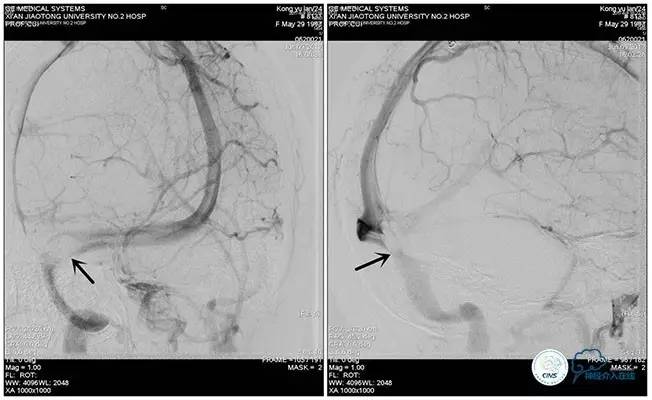

术中右侧ICA造影

右侧ICA斜位及窦内造影

右侧ICA斜位

窦内造影及路图

术中测压:

远端:520mmH2O,

近端:190mmH2O。

治疗方案:

1、8mm×40mm , EverCross球囊扩张;

2、8mm×40mm,Protégé自膨支架成形术。